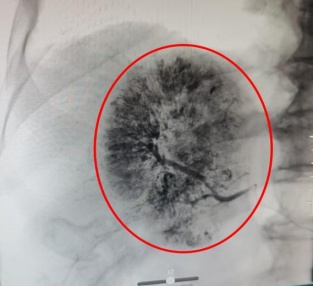

鉴于患者病情危急,传统开腹手术创伤大、风险高,肿瘤微创介入诊疗中心手术团队紧急会诊后,决定为其施行经肝动脉化疗栓塞术(TACE)。术中医生通过股动脉穿刺插入导管鞘,在导丝引导下将导管送至腹主动脉,注入造影剂进行血管造影,清晰显示肿瘤的位置、大小及供血动脉分支。再将微导管选择性插入肿瘤供血动脉,先灌注化疗药物,再注入栓塞剂,精准阻断出血血管,同时切断肿瘤营养供应。术后患者生命体征平稳,腹痛症状明显缓解。复查CT显示,肿瘤出血已完全停止,肿瘤染色消失。

栓塞术前肿瘤染色明显